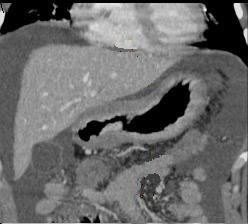

Adenocarcinoma debutant

. Lesion polypoide de la grand courbure .

Image TDM en coupe coronale ( frontale ) |

|

Adeno carcinoma debutant.

Lesion infiltrative , |